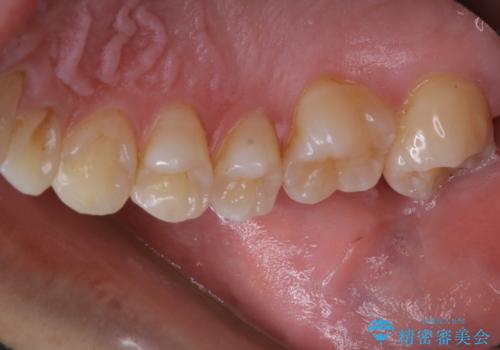

3カ月に1度のPMTCでオーラルケア

- 3カ月ごとに定期的にメンテナンスにいらしている方です。PMTC30分コースを行いました。

PMTC(保険外治療)は、毎日の歯磨きで落としきれない汚れや、タバコのヤニなどの着色も除去します。目には見えない歯と歯の間・歯肉の境目などに残っているプラーク(歯垢)もしっかり取り除きます。